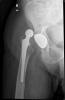

Fractura cuello fémur. Prótesis completa.

Fractura de fémur, prótesis parcial de cadera

Prótesis parcial de cadera